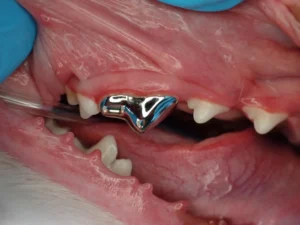

In certain cases, metal crown placement is considered to provide additional protection to teeth that have root canals. This is especially true in police dogs or other working dogs whose teeth are exposed to large chewing forces. We also consider placing a crown in dogs with a history of extensive chewing behavior or when a large part of the tooth has already been broken away.

Most crowns are metal alloy. A silver or gold tint is usually selected. Titanium is an option but is a more difficult metal to work with and cost is sometimes prohibitive. Novel ceramics are selected in people for the esthetics, but in dogs they are prone to breakage.